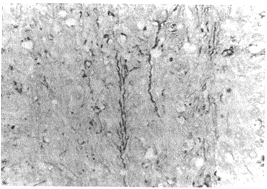

2.2.1 NF染色观察

30min组即可见到脑挫伤灶周围的神经元胞浆内有较多的NF堆积,染成棕褐色;1h组及3h组见神经元胞浆内NF堆积,其数量与30min组相比无明显差别;但在1h组部分神经元轴突呈NF阳性着色,轴突稍增粗,但未见明显扭曲(图1)。6h组仍可在挫伤灶周围的神经元胞浆内见到NF堆积;12h组仅在挫伤灶周围见少量神经元胞浆呈NF阳性着色;48h组NF阳性着色的神经元更少,有的仅见神经元的部分胞浆着色,轴索肿胀、扭曲,并见空泡变(图2)。对照组仅见轴索内呈细丝状均匀排列的NF。

图1 部分神经元轴突呈NF阳性着色,轴突稍增粗,但未见明显扭曲。1hNF×200

图2 轴索肿胀、扭曲,并见空泡变。48hNF×400